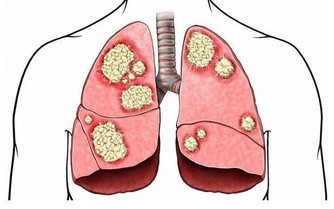

腸易激綜合徵的飲食建議

為什麼一喝冷水一吃辣就拉肚子

如果確定是腸易激綜合徵,應該注意避免易過敏食物、脹氣食物、辛辣食物,如牛奶、豆製品、大豆、扁豆等。

另外,對於腸易激綜合徵患者,減少對腸道的刺激的才是最佳的治療方法。